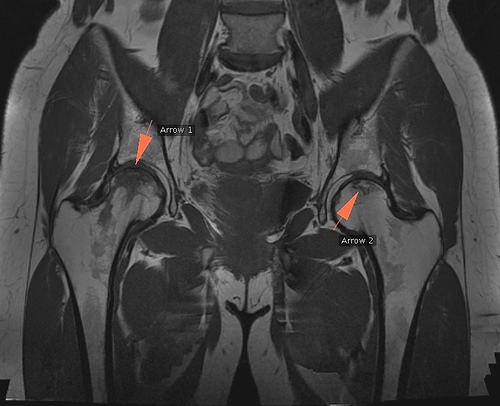

La scintigraphie osseuse et la raisonnance magnétique nucléaire trouve une indication en cas de doute clinique ou d'ostéonécrose de la tête fémorale.

L'IRM est l'examen le plus sensible pour un diagnostic précoce ; les deux hanches sont explorées conjointement vu le risque non négligeable d'atteinte bilatérale.